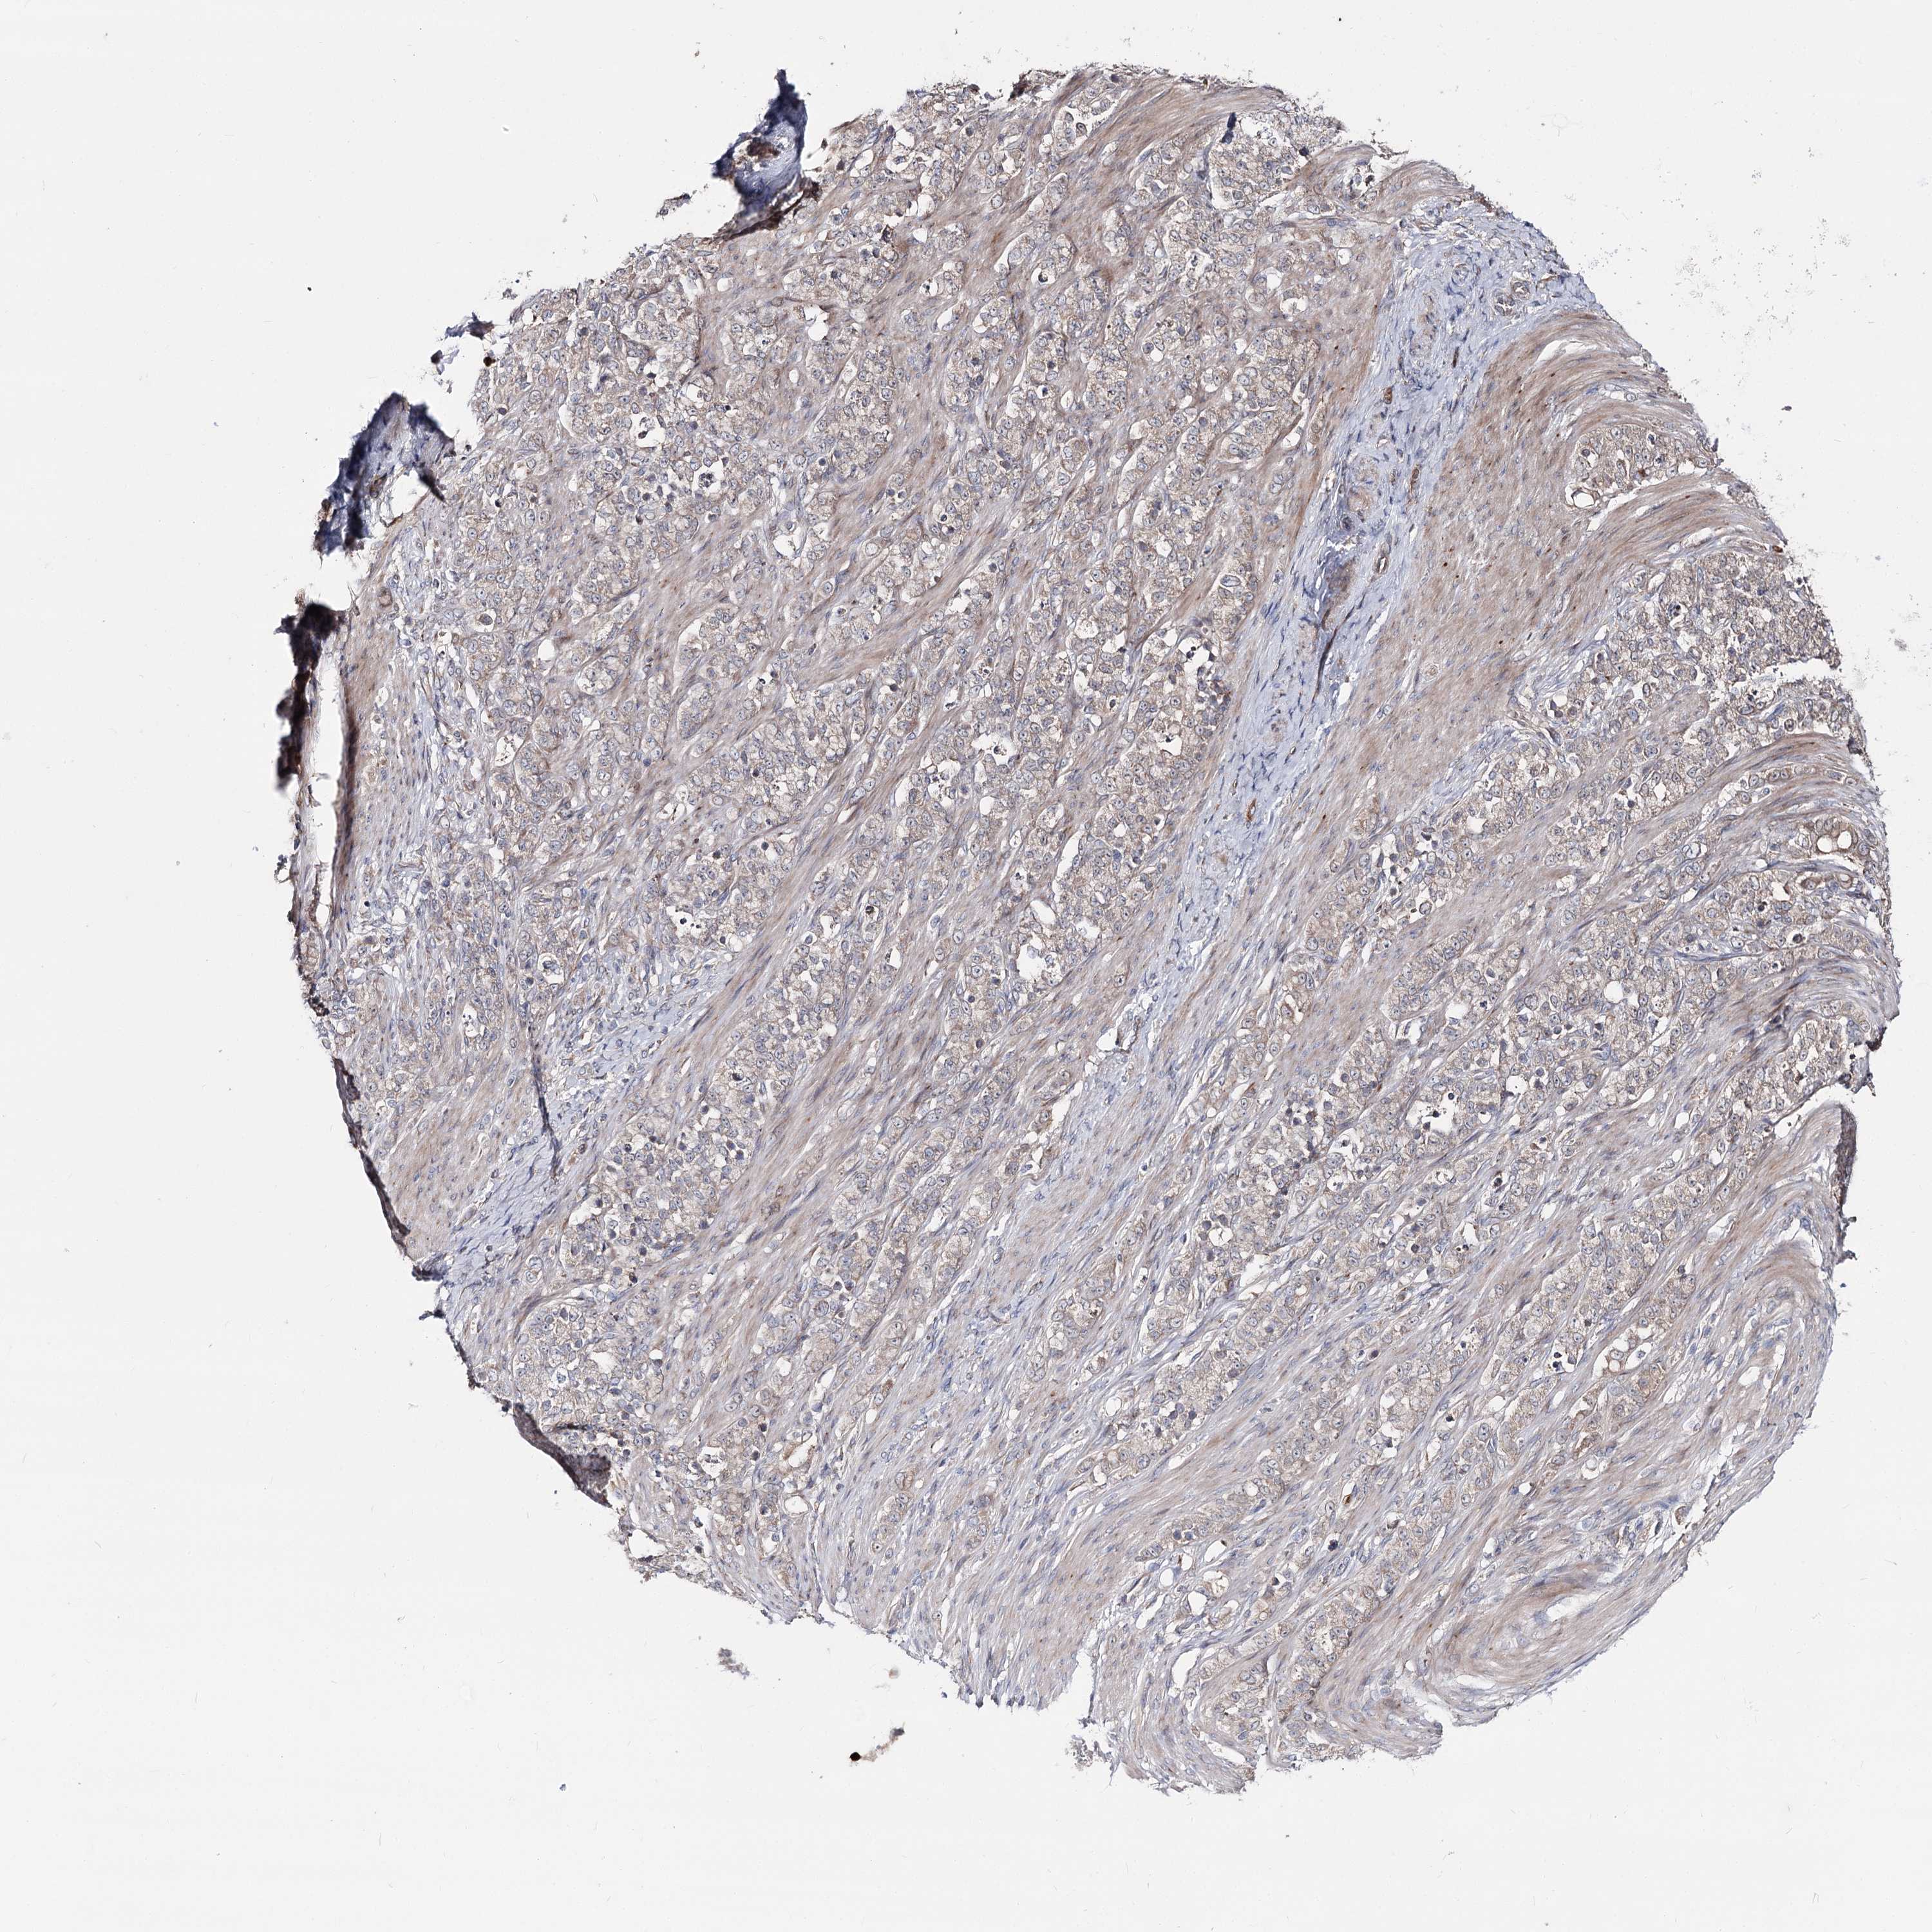

STOMACH CANCER - Protein expressioni

A mouse-over function shows sample information and annotation data. Click on an image to view it in a full screen mode. Samples can be filtered based on level of antibody staining by selecting one or several of the following categories: high, medium, low and not detected. The assay and annotation is described here.

Note that samples used for immunohistochemistry by the Human Protein Atlas do not correspond to samples in the TCGA dataset.

Antibody stainingi

Antibody staining in the annotated cell types in the current human tissue is reported as not detected, low, medium, or high, based on conventional immunohistochemistry profiling in selected tissues. This score is based on the combination of the staining intensity and fraction of stained cells.

Each image is clickable and will lead to virtual microscopy that enables deeper exploration of all samples and also displays staining intensity scores, fraction scores and subcellular localization as well as patient and tissue information for each sample.

Antibody HPA038040

Staining

High

Medium

Low

Not detected

Intensity

Strong

Moderate

Weak

Negative

Quantity

>75%

75%-25%

<25%

None

Location

Nuclear

Cytoplasmic/membranous

Cytoplasmic/membranous,nuclear

Adenocarcinoma, NOS

Adenocarcinoma, High grade